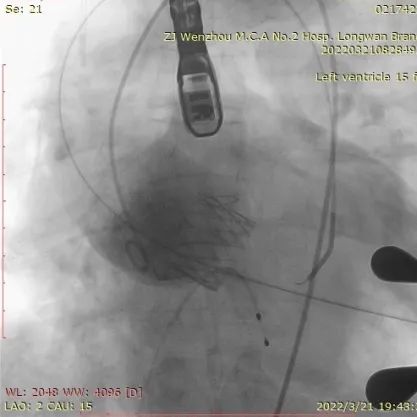

经股静脉置入临时起搏器,并经股动脉植入6F猪尾管。行第五肋间小切口并在心尖部缝制荷包。穿刺心尖后进泥鳅导丝过主动脉瓣经过主动脉弓到达降主动脉膈肌水平。单弯管交换硬导丝后,用16F扩张鞘预扩心尖穿刺处,后将 J-Valve瓣膜(27mm)装入输送器并经心尖穿刺处推送至主动脉根部,释放定位件,并微调角度使其入窦,后完全释放瓣膜,撤出输送器。通过DSA和TEE观察人工瓣膜膨胀后金属支架的形态、位置,有无瓣周漏。撤出导丝,收紧心尖处荷包线并打结,后鱼精蛋白中和肝素,彻底止血,逐层关胸,封皮,拔出股动脉鞘并在股动脉穿刺处压迫止血。手术过程顺利,患者生命体征平稳。

术中影像监护与评估(DSA&TEE)

瓣膜释放泥鳅导丝和单弯管过弓

加硬导丝建立轨道

介入器过瓣环平面

释放定位件

瓣膜入座

瓣膜自膨

松开锁丝,撤出输送器

DSA和TEE显示无瓣周漏,瓣膜位置、形态良好